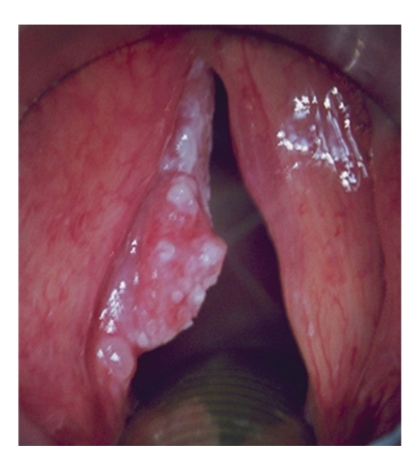

Glottis

Meestal vroegtijdig symptomen: heesheid.

Stridor bij grotere tumoren

T1 ware stembanden

T2 uitbreiding naar supra/subglottis, vertraagde

mobiliteit

T3: gefixeerde stemband (ingroei in

spier/gewricht)

T4: doorgroei doorheen kraakbeen van larynx

T1/T2: radiotherapie of chordectomie of

partiële laryngectomie

T1/T2

Goede prognose

(T1>90% 5j)

Radiotherapie

Laser cordectomie. → via mond stukjes tumor wegnemen

geen mucosale golf meer = tumor tot spier → met laser